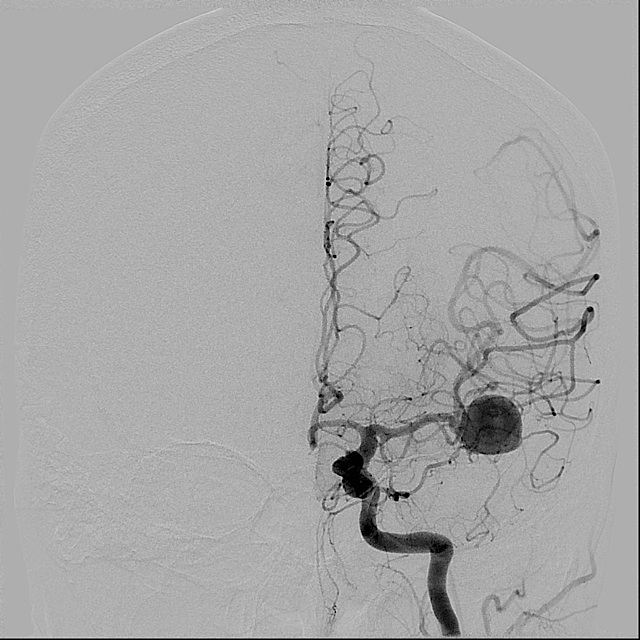

Túi phình động mạch não giữa bên trái (mũi tên đỏ) trên hình chụp CT mạch máu não và hình chụp mạch máu não thông thường của bệnh nhân bị xuất huyết dưới nhện.

Hình chụp CT mạch máu não của bệnh nhân bị xuất huyết dưới nhện do có túi phình động mạch thông trước (mũi tên đỏ).